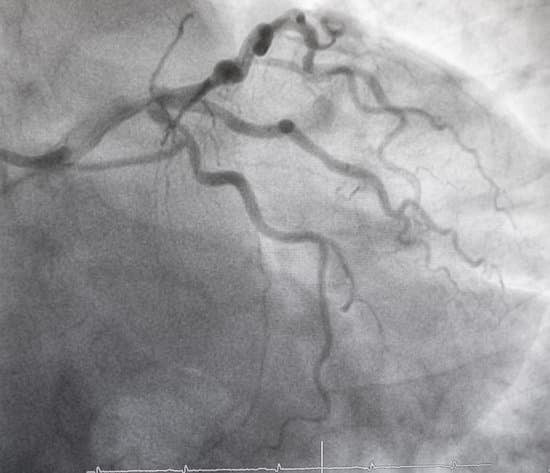

심혈관 조영술(Coronary Angiography)은 관상동맥을 포함한 심장 혈관의 상태를 시각적으로 평가하기 위한 영상 검사입니다.

이 검사는 주로 관상동맥 질환(심장에 혈액을 공급하는 혈관이 좁아지거나 막히는 질환)을 진단하는 데 사용됩니다.

심혈관 조영술은 X-ray 기기와 조영제를 이용해 심장 혈관 내부의 상태를 확인하여 협심증, 심근경색 등의 위험을 진단하고 치료 계획을 세우는 중요한 검사입니다.

조영제 주입: 카테터를 통해 조영제를 주입하여 혈관 내부를 확인합니다. 조영제가 주입되면 혈관이 X-ray 기기에 의해 선명하게 보이게 되어 혈류 흐름을 평가할 수 있습니다.

X-ray 촬영: 조영제를 주입하면서 X-ray 영상을 촬영해, 혈관의 협착 부위나 막힌 부위를 시각적으로 확인합니다.